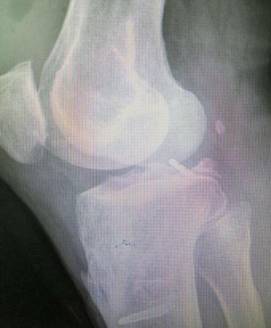

术前术后对比

全膝关节翻修术

全髋关节翻修术